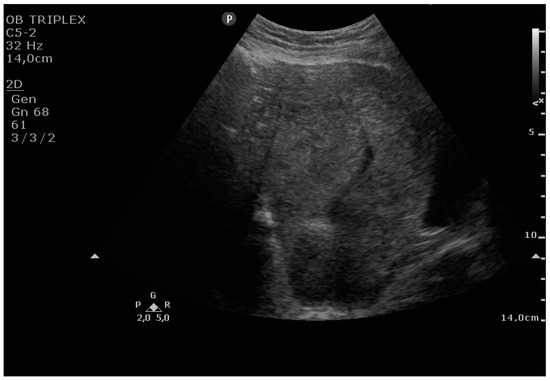

The PUUS method evaluates the proportion of the endometrial length occupied by blood or debris, as follows (Figure 1, Figure 2, Figure 3, Figure 4 and Figure 5):

Figure 5. Grade 4: over three-quarters of the endometrial length occupied by blood or debris.